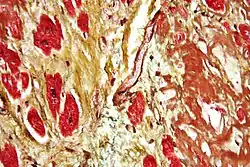

| Micrograph of a heart with fibrosis (yellow) and amyloidosis (brown). Movat's stain. | |